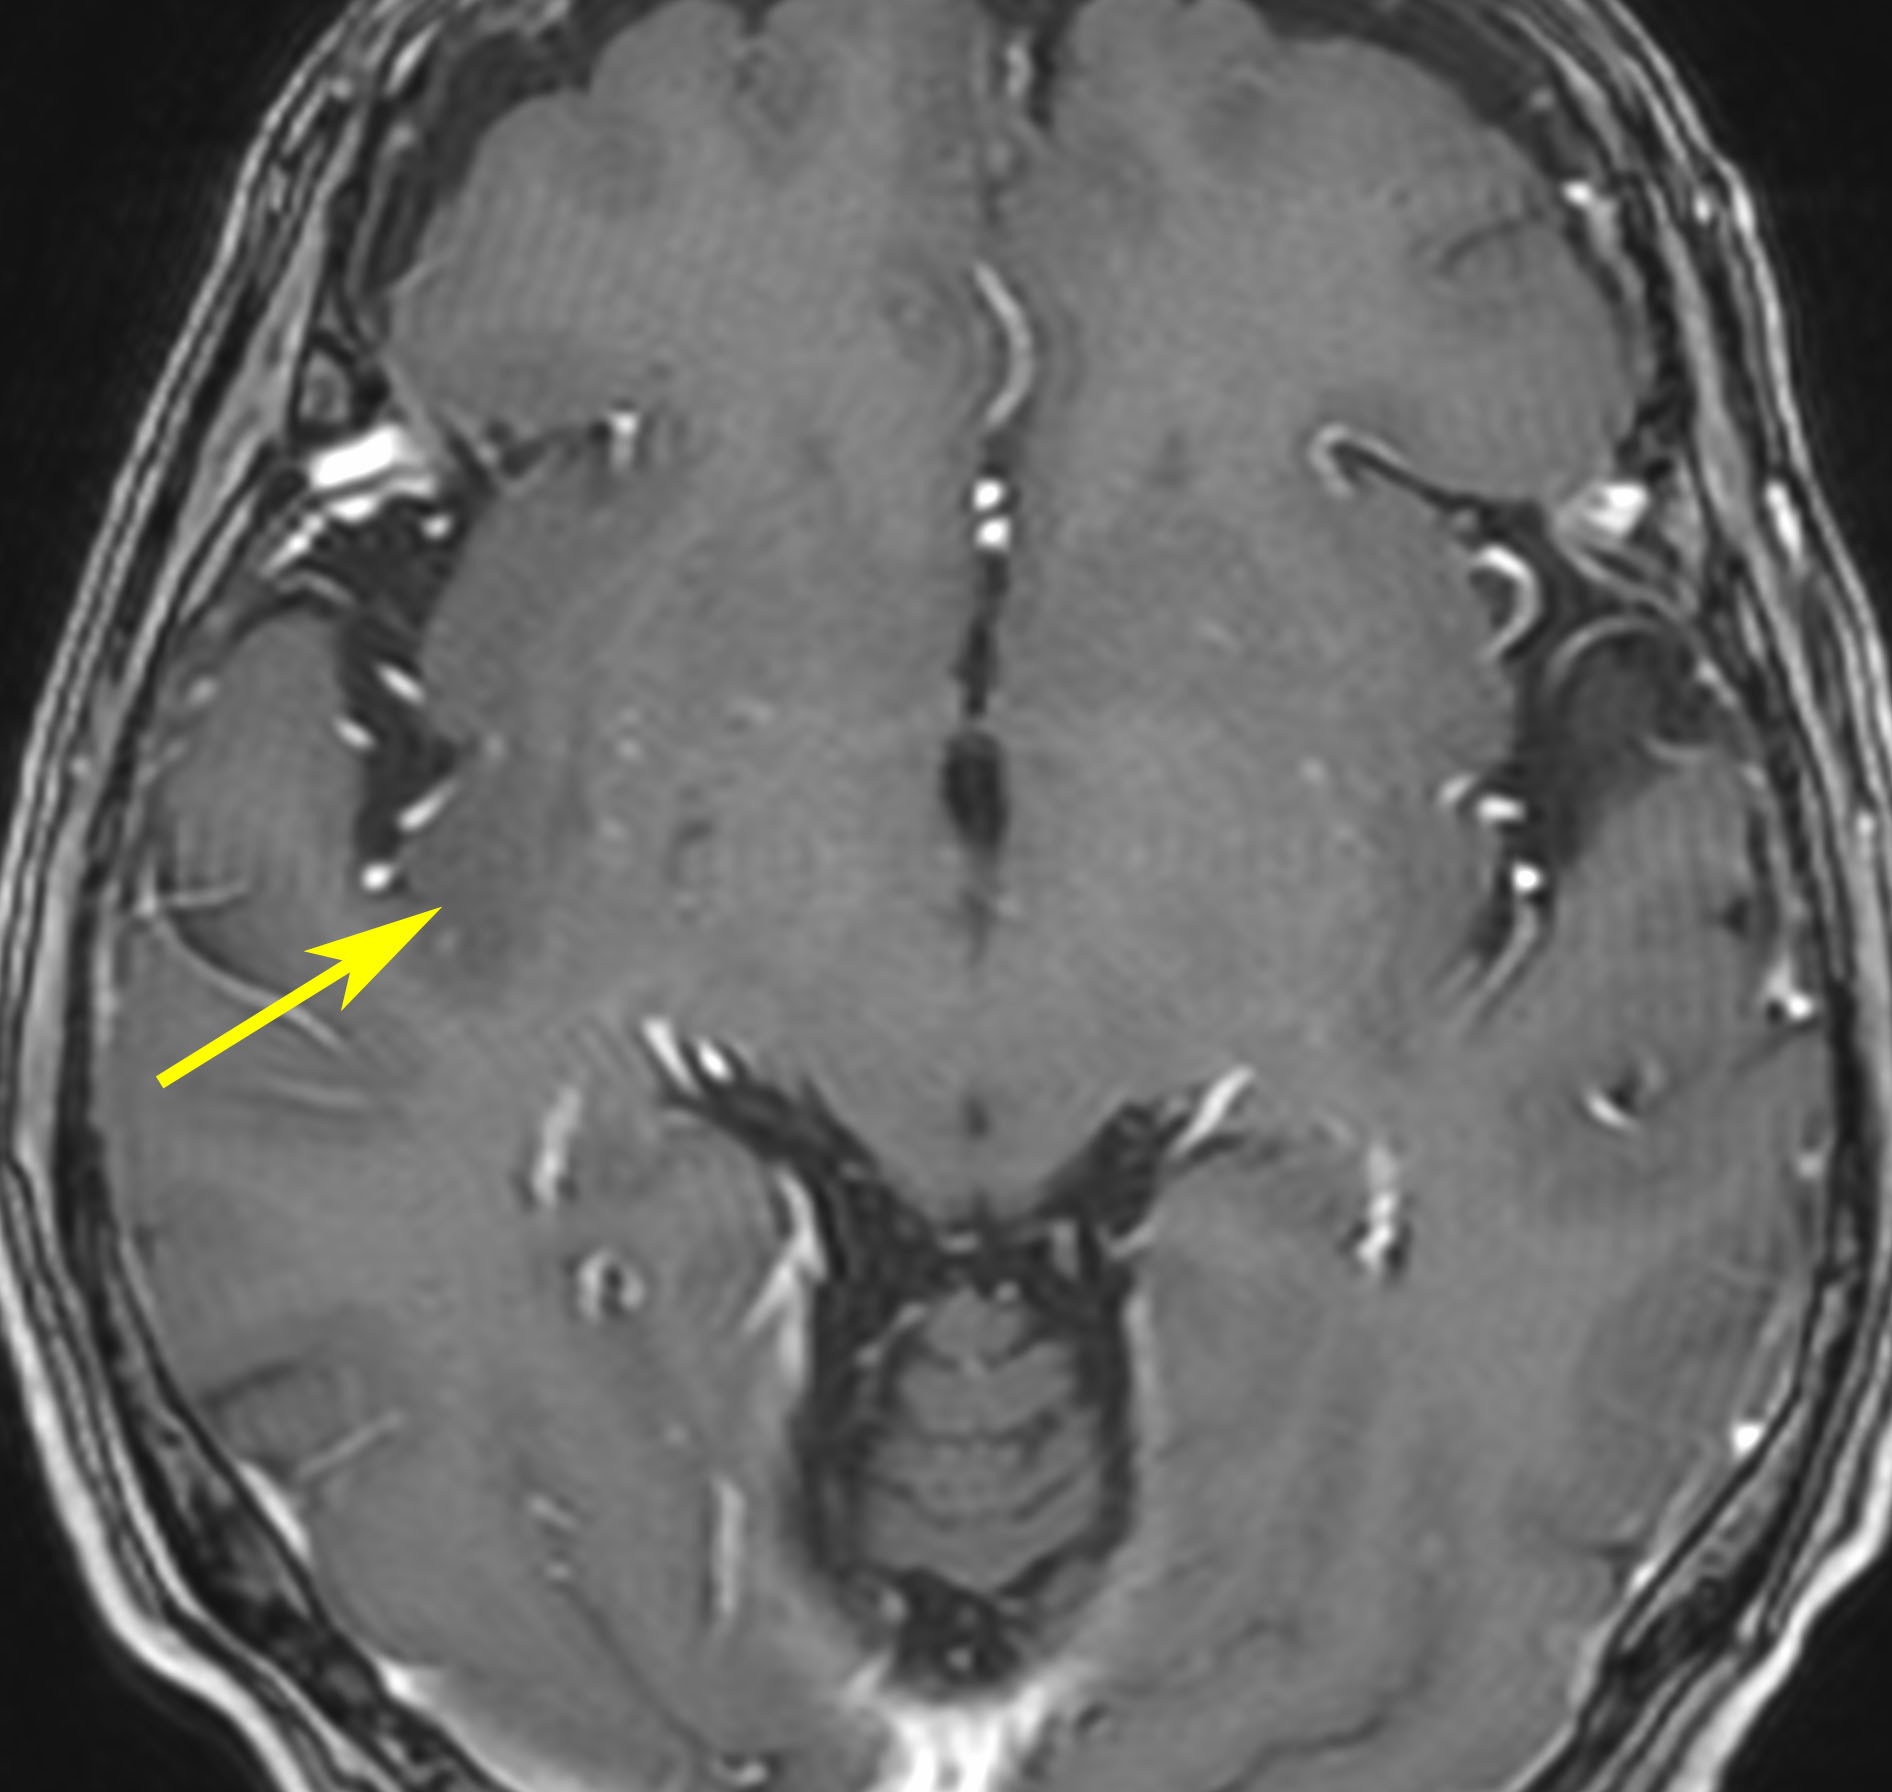

右側頭葉島の病変です。1年間の経過ではっきり増大したので,無症状でしたが生検術を行いました。病理組織では,異型グリアの増殖はありましたが,核分裂蔵,血管内皮の増生や壊死は明らかではありませんでした。しかし,遺伝子診断ではIDH1/2 野生型,ATRX retained,TERT promotor野生型,1p/19q共欠失なしでした。膠芽腫という確定病理診断です。

標準治療を加えましたが,数ヶ月後に急激な増大を呈しました。グレード4の臨床像です。MRI画像よりも病理組織像よりも,遺伝子診断の方がより性格に予後を示す例です。